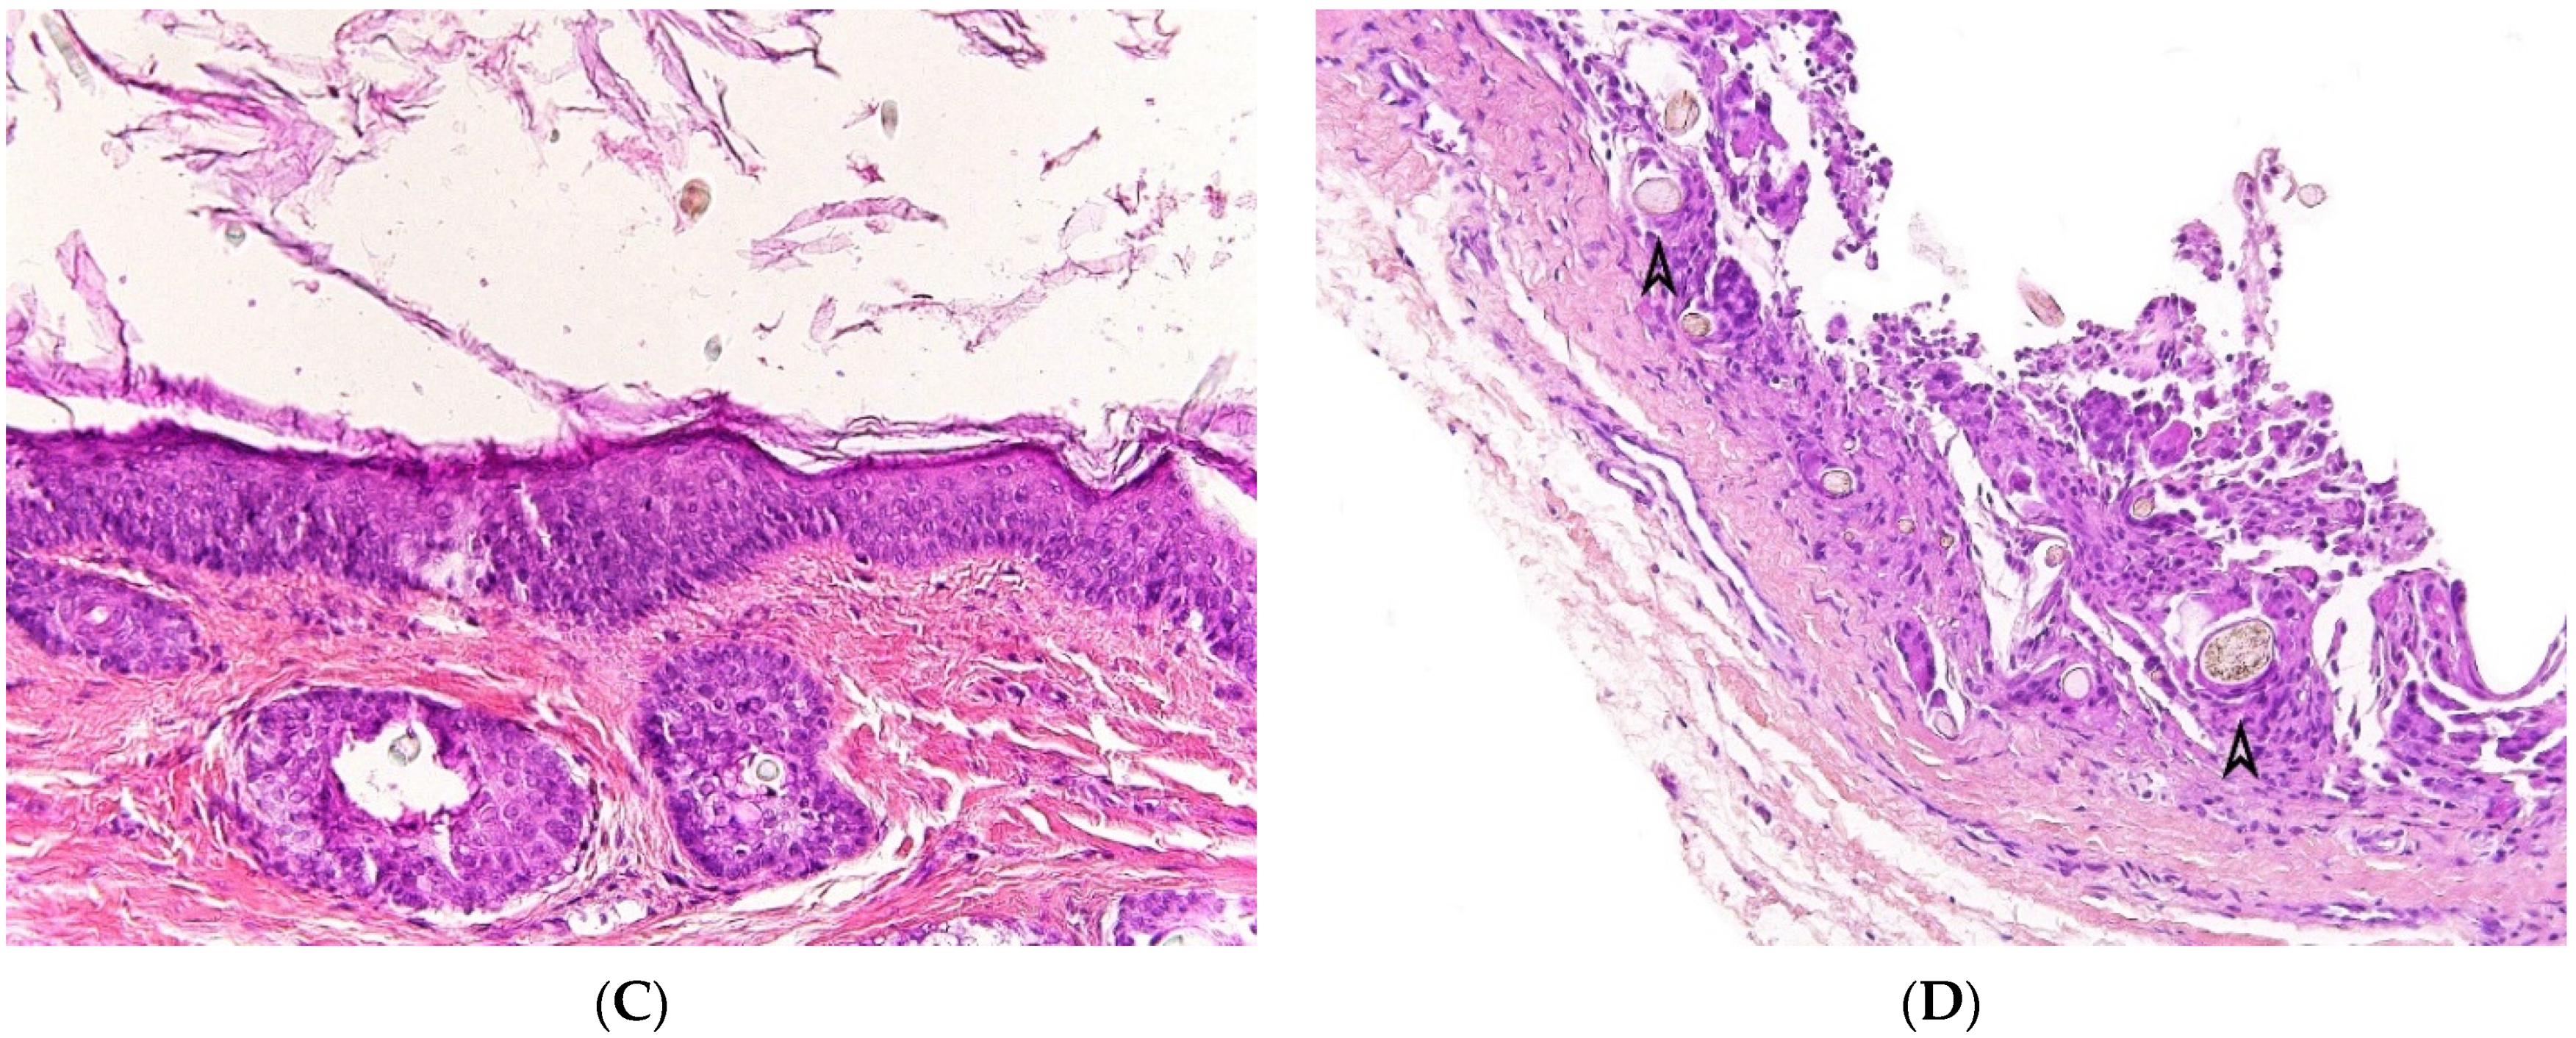

2.4.2. Histopathological Features

At gross examination, the cyst has yellowish-white keratinous material and might reach 12 cm in size. They are lined by stratified squamous epithelium with associated small hair follicles and sebaceous glands (Figure 5A,B). Eccrine sweat glands and apocrine glands are less commonly present. The cavity contains laminated keratin and numerous vellus hairs oriented haphazardly (Figure 5C). Acute inflammation may result in the subsequent disruption of the cyst wall, with the development of an intense foreign body giant cell reaction (Figure 5D).

Figure 5.

Dermoid cyst. (A) (H.E.S). The cyst is lined by keratinizing stratified squamous epithelium. (B) (H.E.S). The cyst is deeply located in the subcutis. Small hair follicles and sebaceous glands are attached to the epithelium. (C) (H.E.S). The lumen contains numerous vellus hair shafts and lamellated keratin, and the epithelium has a granular layer. (D), (H.E.S). Several vellus hairs (arrowheads) are observed within the granuloma.